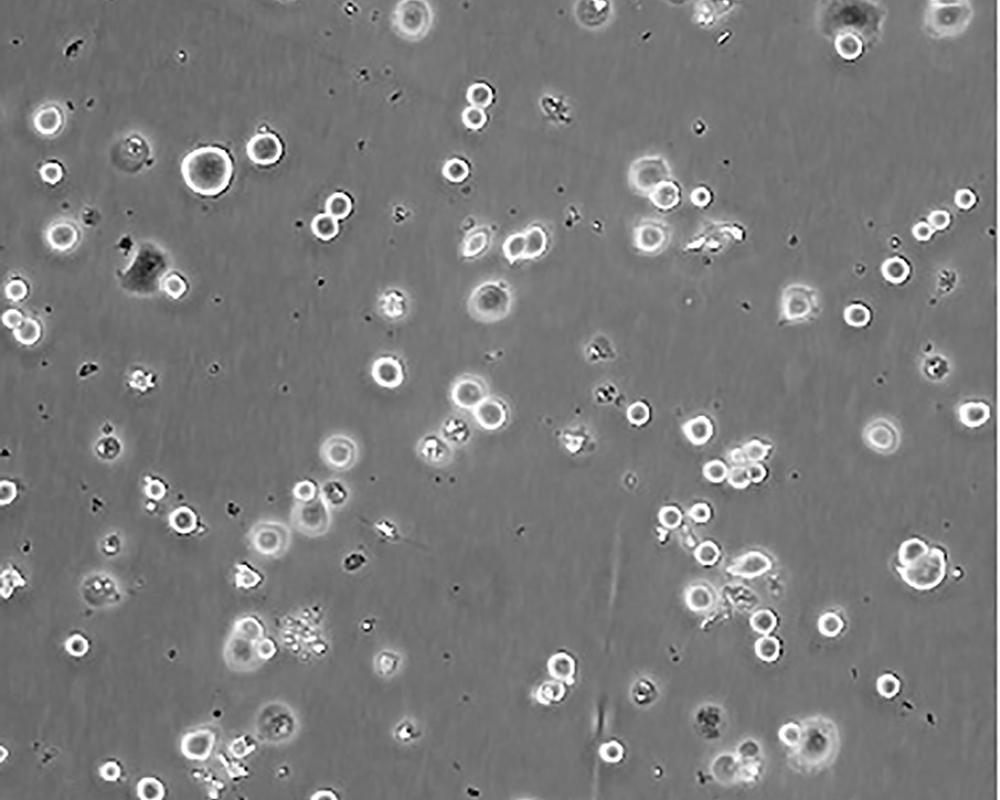

SK-BR-3 [SKBR-3;SKBR3]

產(chǎn)品名稱 SK-BR-3 [SKBR-3;SKBR3]

中文名稱 人乳腺腺癌細(xì)胞

組織來源 mammary gland/breast; derived from metastatic site: pleural effusion

生長特性 adherent

形態(tài)特征 epithelial

細(xì)胞描述 he patient, a White, Caucasian female, age 43, blood type A+, had been treated with radiation, steroids, cytoxan and 5-fluorouracil.No virus particles.Ultrastructural features include microvilli and desmosomes, glycogen granules, large lysosomes, bundles of cytoplasmic fibrils.The SKBR- 3 cell line overexpresses the HER2/c-erb-2 gene product.